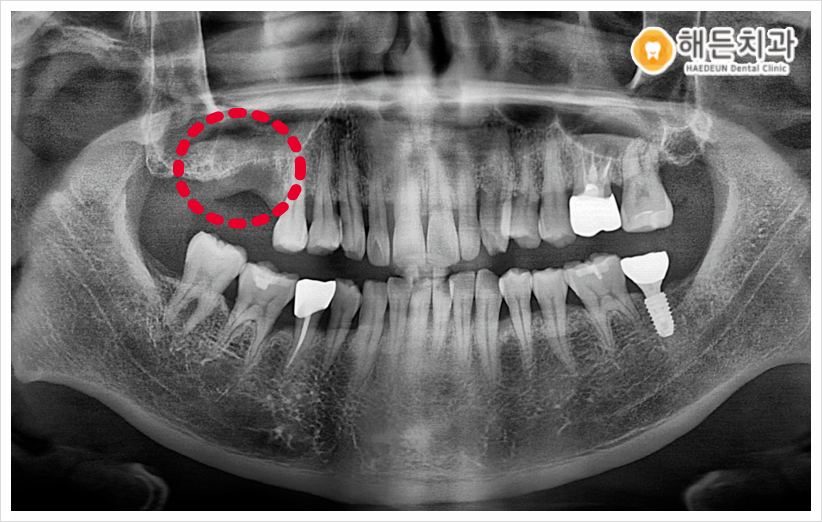

오늘 소개해 드릴 분께서는 오른쪽 위 어금니 부분의 치아 상실로 평소 한쪽으로만 식사를 하고 계신다며 임플란트 상.담을 위해 본원을 찾아주셨는데요.

정밀한 검진을 위해, 우선 파노라마 사진을 촬영해 확인해보았습니다.

치아가 상실된 부위의 잇몸뼈가 많이 얇고, 또한 상악동이 내려와 있어서 임플란트를 심기에는 잇몸뼈가 충분하지 않았습니다.

.

이 상태로 임플란트를 식립하게 된다면 픽스쳐(인공치근)의 고정력이 떨어져 흔들리거나 빠질 수도 있기 때문에 환자분의 경우 상악동 거상술+뼈이식을 동반한 임플란트 식립이 필요했습니다.